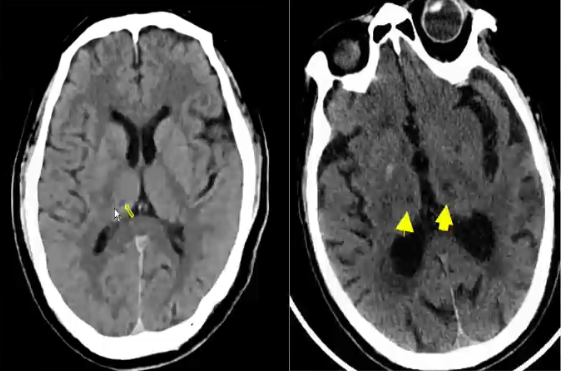

丘脑腔隙性梗死

影像学表现-CT表现:CT上表现为丘脑区类圆形低密度病灶,边界清楚或不清,直径多为10-15mm。占位效应轻,一般仅有相邻脑室局部受压,多无中线结构移位。注射对比剂有些可见病变区结节样强化。